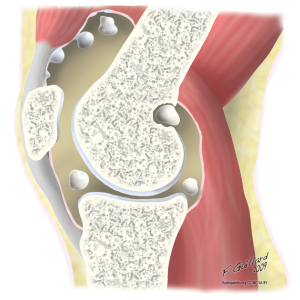

Хондроматоз коленного сустава достаточно редкое заболевание, при котором наступает перерождение участков синовиальной оболочки сустава. В ней образуются костные или хрящевые тела.

Вначале они фиксированы к синовиальной оболочке, но могут отщепляться и свободно перемещаться в полости коленного сустава (свободные хондромные тела). Размер хондромных тел достигает 5см.

Спровоцировать заболевание могут физические нагрузки, травмы, инфекционные процессы. Вначале в синовиальной оболочке образуются хрящевые узелки, которые могут увеличиваться в размере и по мере отделения от оболочки становятся свободными. Синовиальная оболочка утолщается, имеется хроническое воспаление, которое приводит к развитию синовита.